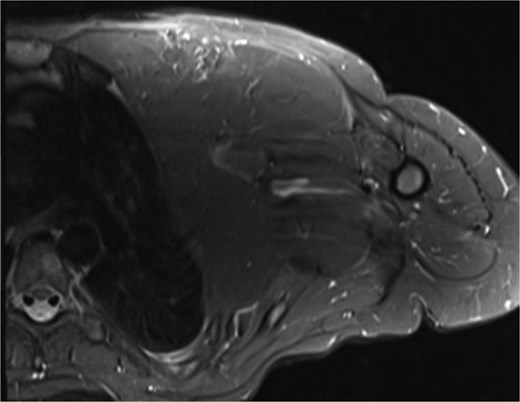

A 22-year-old female presented with progressive swelling in the left anterior chest wall above the left breast, associated with needle-like chest pain, left upper limb tingling, and weakness. The patient had a history of childhood cystic hygroma in the left axilla, previously excised. She denied constitutional symptoms but reported compressive symptoms such as shortness of breath, dysphagia, and hoarseness. A family history of breast cancer with thyroid metastasis was noted in her mother. On examination, the patient exhibited multiple bilateral solitary thyroid nodules and a bulky swelling in the left anterior chest and axilla. Computed tomography (CT) imaging (Fig. 1) revealed hypodense bilateral thyroid nodules, with magnetic resonance imaging (MRI) (Fig. 2) showing an enhancing left axillary lesion (2 cm, previously 1 cm) and an anterior chest wall lesion (1 cm). The mass, measuring 23 × 8 cm, extended to the lower left neck, left chest wall, and left axilla, encasing the neurovascular bundle without muscle or osseous invasion (Fig. 3). Fine-needle aspiration (FNA) cytology (Fig. 4) of the right thyroid nodule indicated atypia of undetermined significance (Bethesda III), while left-sided nodules and biopsies from the axilla, breast, and neck confirmed benign mature adipose tissue. The patient underwent total thyroidectomy, level V left neck exploration, and excision of lipomatous masses from the axilla, anterior chest, and breast, involving multiple surgical teams. Intraoperatively, vocal cords were preserved, and clear planes for lipoma excision were identified. The total excised lipomatous tissue weighed 13.57 kg (Fig. 5). Pathological examination confirmed mature adipose proliferation with no malignancy. Fluorescence in situ hybridization (FISH) ruled out MDM2 amplification, and genetic testing returned negative. Postoperatively, the patient developed deep vein thrombosis (DVT) in the left upper limb, diagnosed via Doppler study, and was treated with low-molecular-weight heparin (LMWH) followed by rivaroxaban. Follow-up MRI at 2 days and 3 months confirmed no residual or recurrent tissue growth. The patient started levothyroxine for thyroid function management and monitored for optimal dosing.

Interval increase in size of the large left upper lateral cervical, sub-pectoral, and axillary region fatty lesion protruding beyond the pectoralis major muscle into the upper breast region, keeping with lipomatosis.

Left chest wall lipomatosis with extension to the left neck and left axilla with thin septations, and there is a small enhancing focus (within the fatty lesion) which could be a small enhancing nodule or lymph node. The overall measurement has relatively increased (consider patient maturation).

Partially scanned left thoracic lipomatosis extending to the lower neck with mild mass effect over the left internal jugular vein. A multilocular goiter with a complex thyroid nodule is noted in the lower neck.